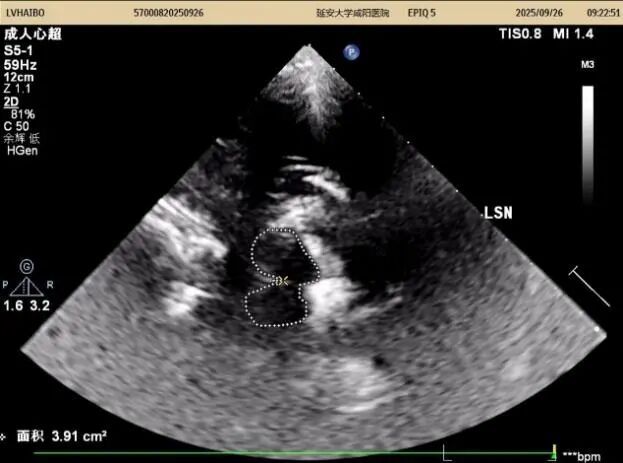

26日上午及下午14:00至15:50,以实际病例为媒介全流程质控,从设备调试、探头的选择与放置、中脑(黑质、红核、导水管)、丘脑、第三脑室、豆状核区域等的识别,到图像优化与测量规范,逐步演示标准操作流程,重点解析黑质高回声的识别与鉴别诊断。期间,结合患者病史,耐心答疑、细致指导,引导医师多维度理解技术要点,提升实战能力。同时对我科前期工作给予高度评价。

在专题授课环节,张教授以《帕金森病的TCS与神经调控专家共识-解读与临床应用》为题,从帕金森病的发病率及早期诊断难点切入,以问题为导向,结合国内外研究,系统讲解了中脑黑质超声的设备要求、检查体位、标准切面及关键核团评估要点,并通过典型图像与病例,深入阐释影像特征与临床表现的关联。针对实际工作中常见问题进行了重点强调,现场学术气氛浓厚。王英莉主任总结指出,开展TCS需做到“准、慢、细”—诊断精准、随访耐心、观察细致,并强调各亚专业组应加强与临床科室的纵深交流,融入科研思维。